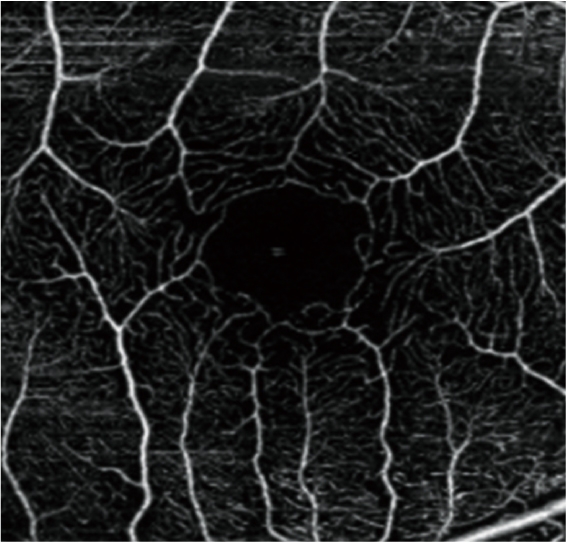

血流OCT在精細(xì)模式下可提供高分辨率圖像,以助于提高診斷率。

自動全景成像(可達(dá)12 x 12 mm)

本軟件可自動合成區(qū)域范圍可達(dá)12 x 12 mm的全景圖像。

圖片由鹿兒島大學(xué)醫(yī)院(Kagoshima University Hospital)提供